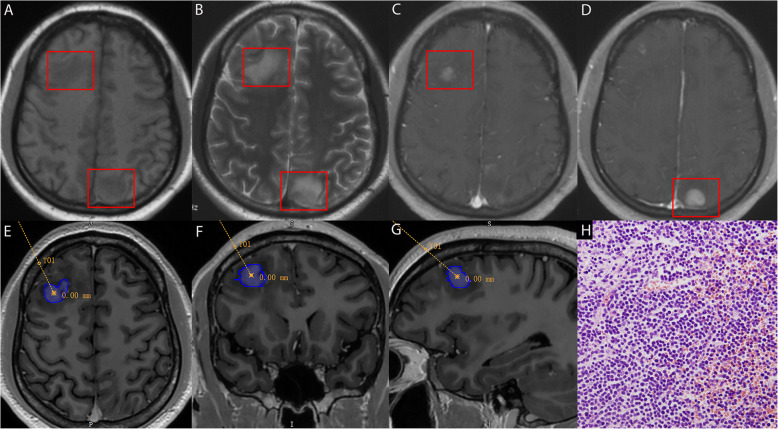

Methods: We retrospectively collected clinical data from 22 patients with LCL and analyzed their magnetic resonance imaging and pathological characteristics. Pathological diagnoses were made using stereotactic intracranial puncture biopsy.

Results: Between April 2003 and December 2023, 22 patients with LCL were admitted, including 18 males and 4 females aged 7-71 years. Bone marrow aspiration identified 14 cases of acute lymphoblastic leukemia (ALL), one of chronic lymphoblastic leukemia, six of acute myeloid leukemia (AML), and one of chronic myelomonocytic leukemia (CMML). Most patients presented with non-specific symptoms, including headache, nausea, vomiting, limb convulsions, and changes in mental status. A few patients had localized neurological deficits, such as limb weakness and blurred vision. Common systemic symptoms included fever, night sweats, and weight loss. The pathological diagnoses of the 22 patients were CNSL in 13 patients, CNS infections in five patients, and neurodegenerative diseases in four patients. Discrepancies were found between the clinical and pathological diagnoses in eight cases.

Conclusions: Stereotactic intracranial lesion biopsy is minimally invasive, safe, convenient, and critical in the early and differential diagnosis of LCL. Early identification of the lesions' nature and timely implementation of accurate and precise treatments can improve patient prognosis.